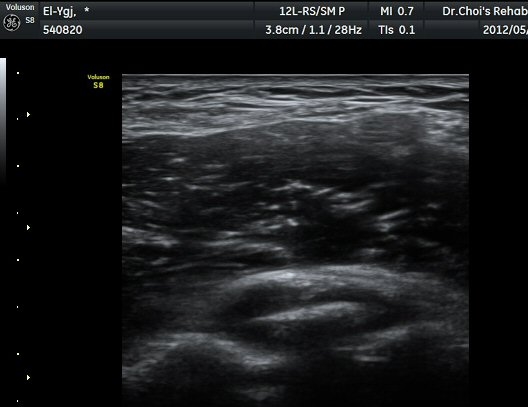

ÁֵοÍ(olecranon fossa) Á¾´Ü¸é°Ë»ç¿Í Ⱦ´Ü¸é°Ë»ç¿¡¼­ ÁÖµÎ¿Í ¼ö¾×Àú·ù¿Í °ø¿¡ÄÚ »À µ¢¾î¸®°¡

°üÂûµÈ´Ù(±×¸² 4, 5, 6).